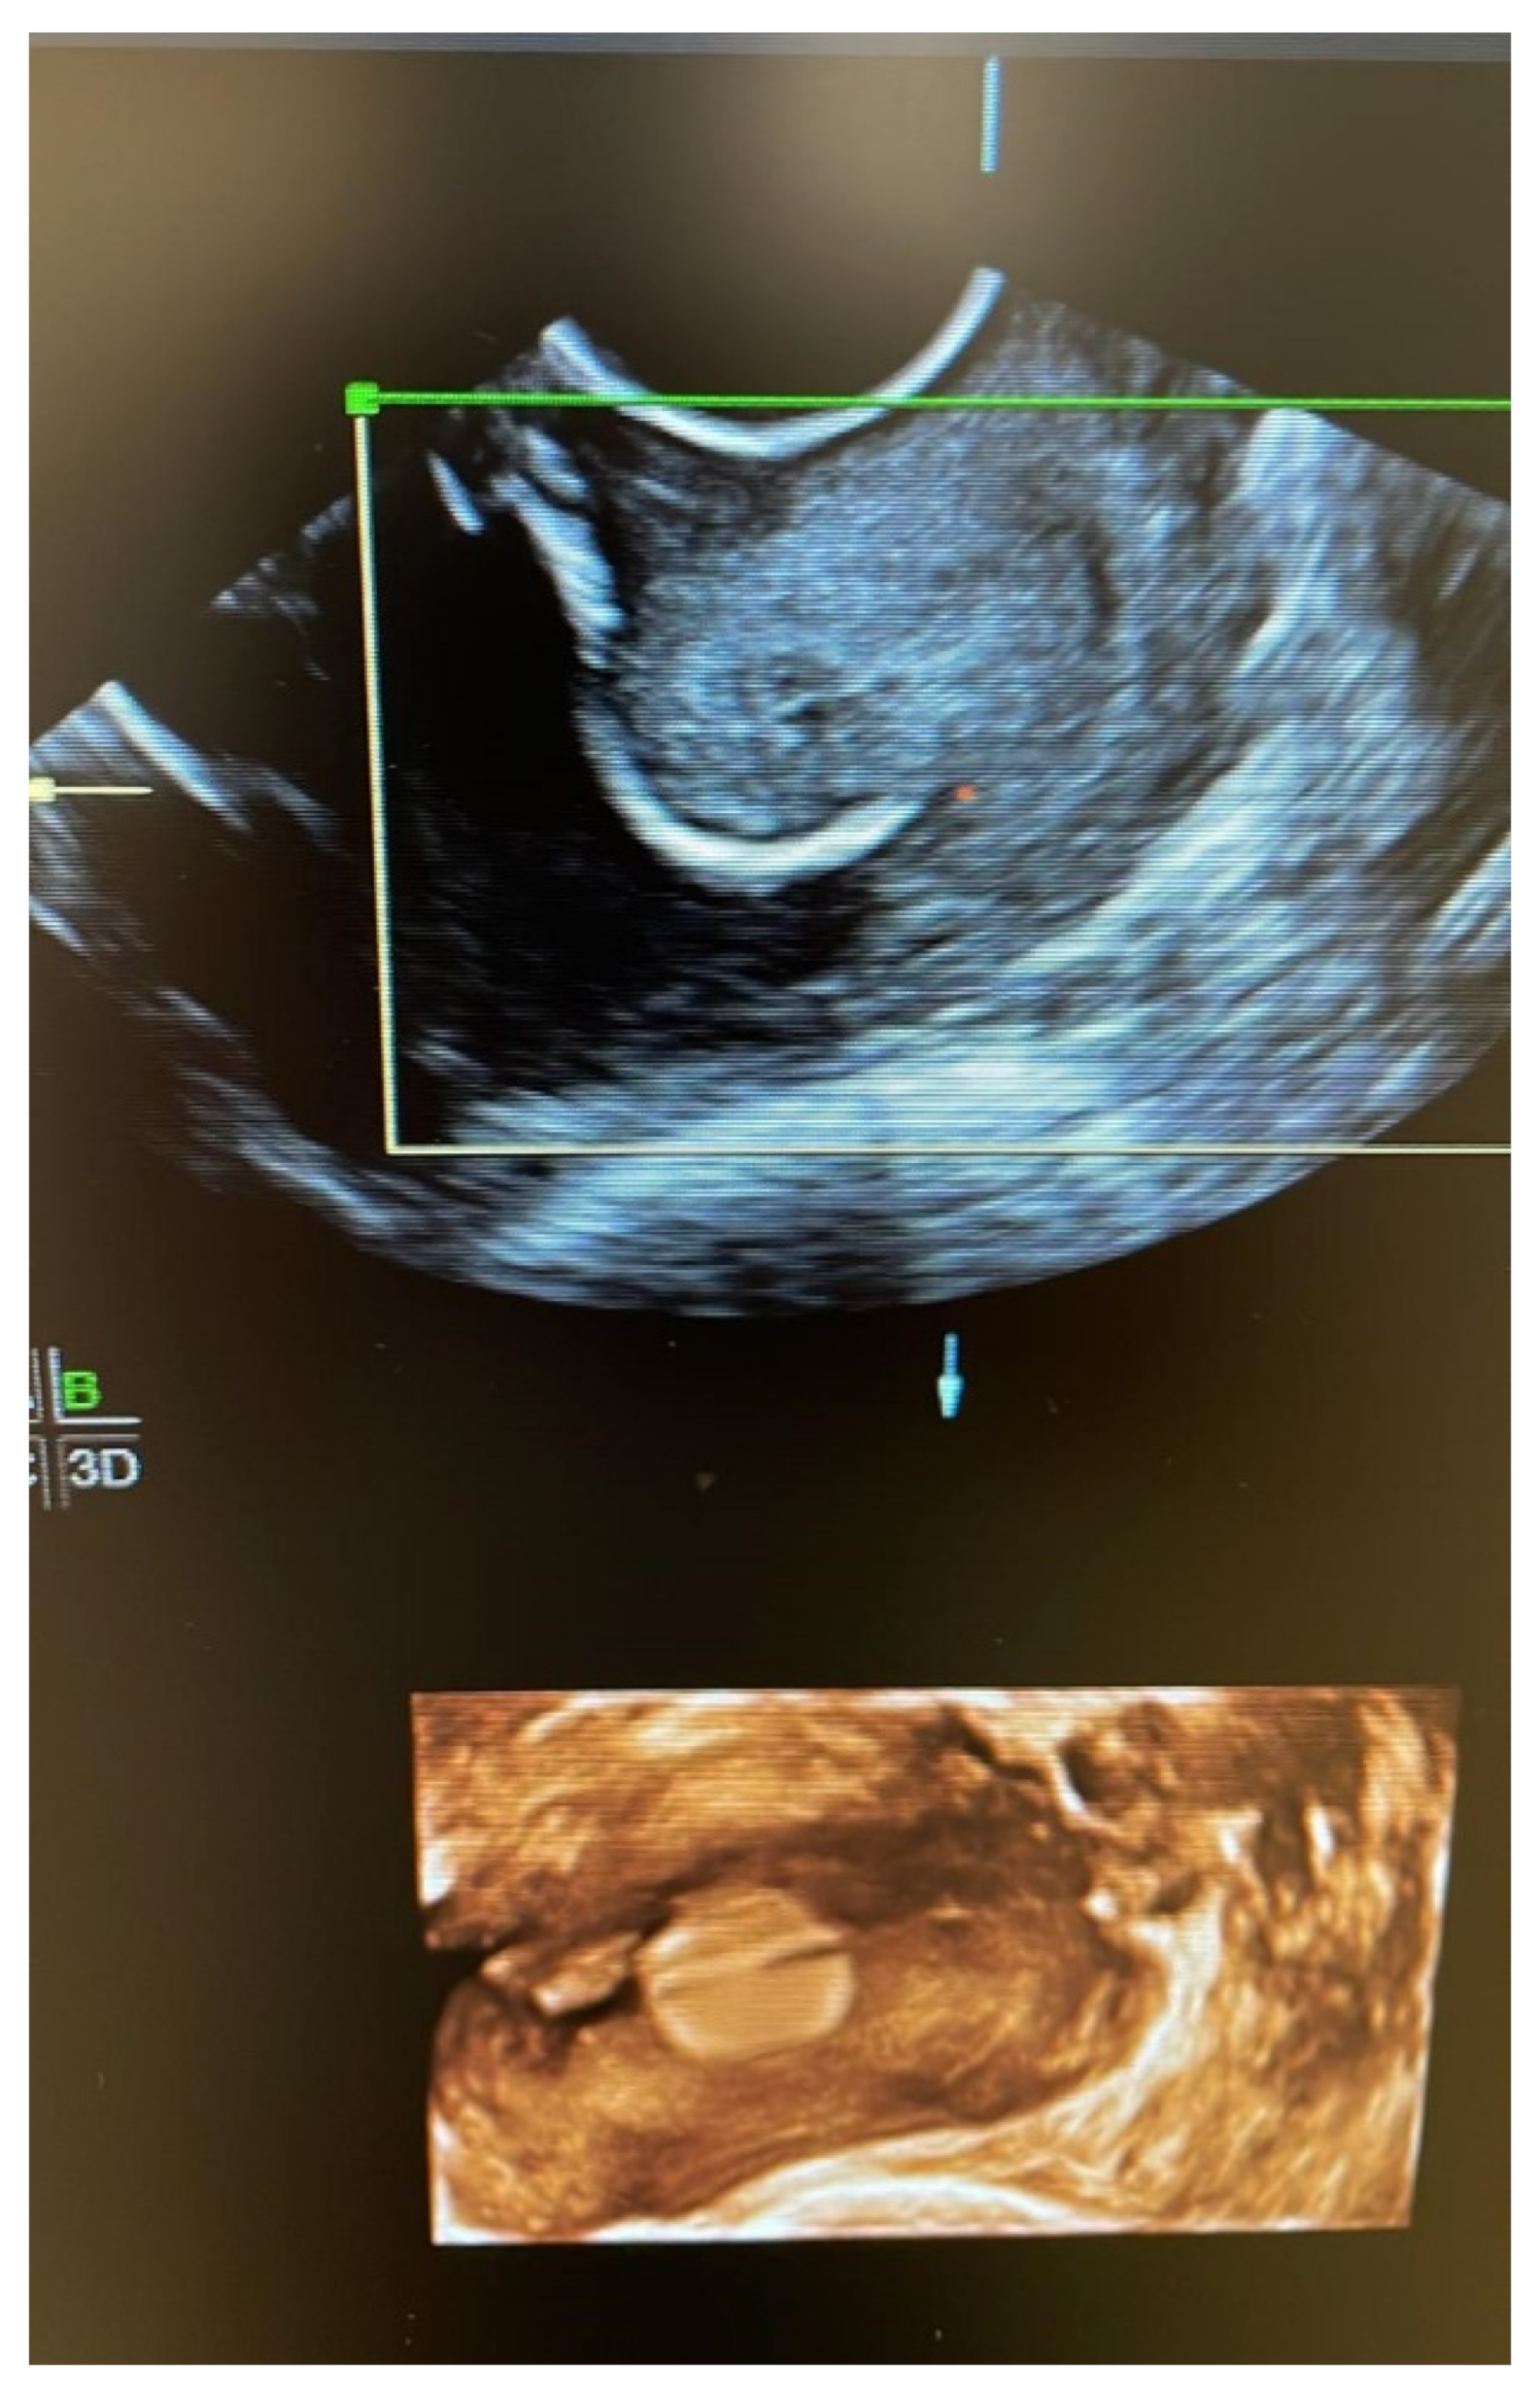

- The Foley catheter was inserted and then filled depending on the degree of cervical dilation and the stage of the procedure. For this, a third assistant helped to increase or reduce the drainage flow, depending on the stage of the procedure, which initially corrected the prolapse. The drainage flow was then reduced to cross the cervical canal, and later, once past the internal cervical os, the volume was increased again to reduce the bag and facilitate safe cerclage (Figure 1).